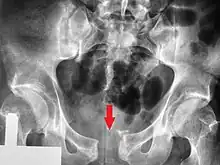

.png.webp)

Pelvic fractures are most commonly described using one of two classification systems. The different forces on the pelvis result in different fractures. Sometimes they are determined based on stability or instability.[8]